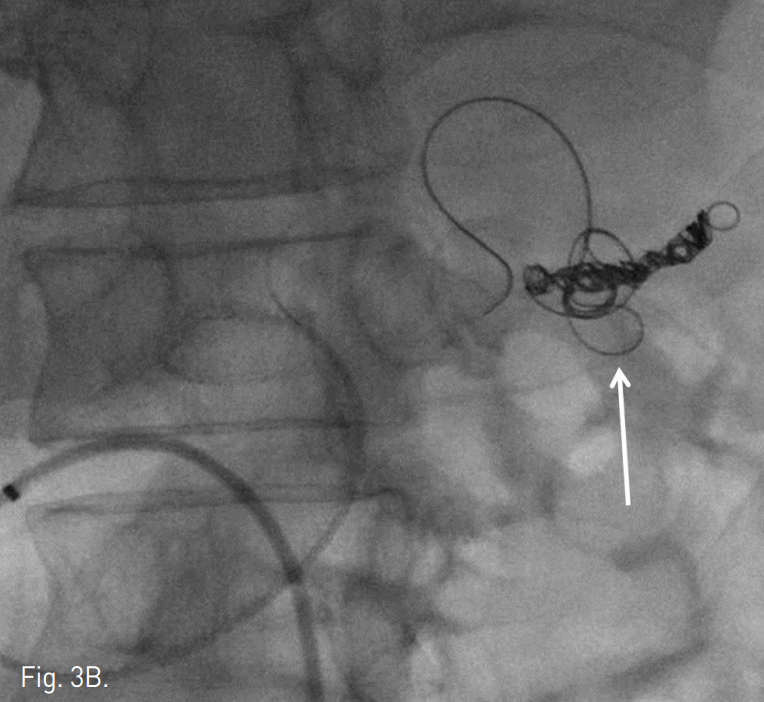

Fig. 3

Radiographs obtained during embolization. One of distal branch of splenic artery was embolized with IDC coils (arrow in A). The distal neck of aneurysm was embolized by multiple IDC coils (arrow in B), which was anchored to the small distal branch of splenic artery. Further embolization of proximal neck and part of aneurysmal sac was done (arrow in C).